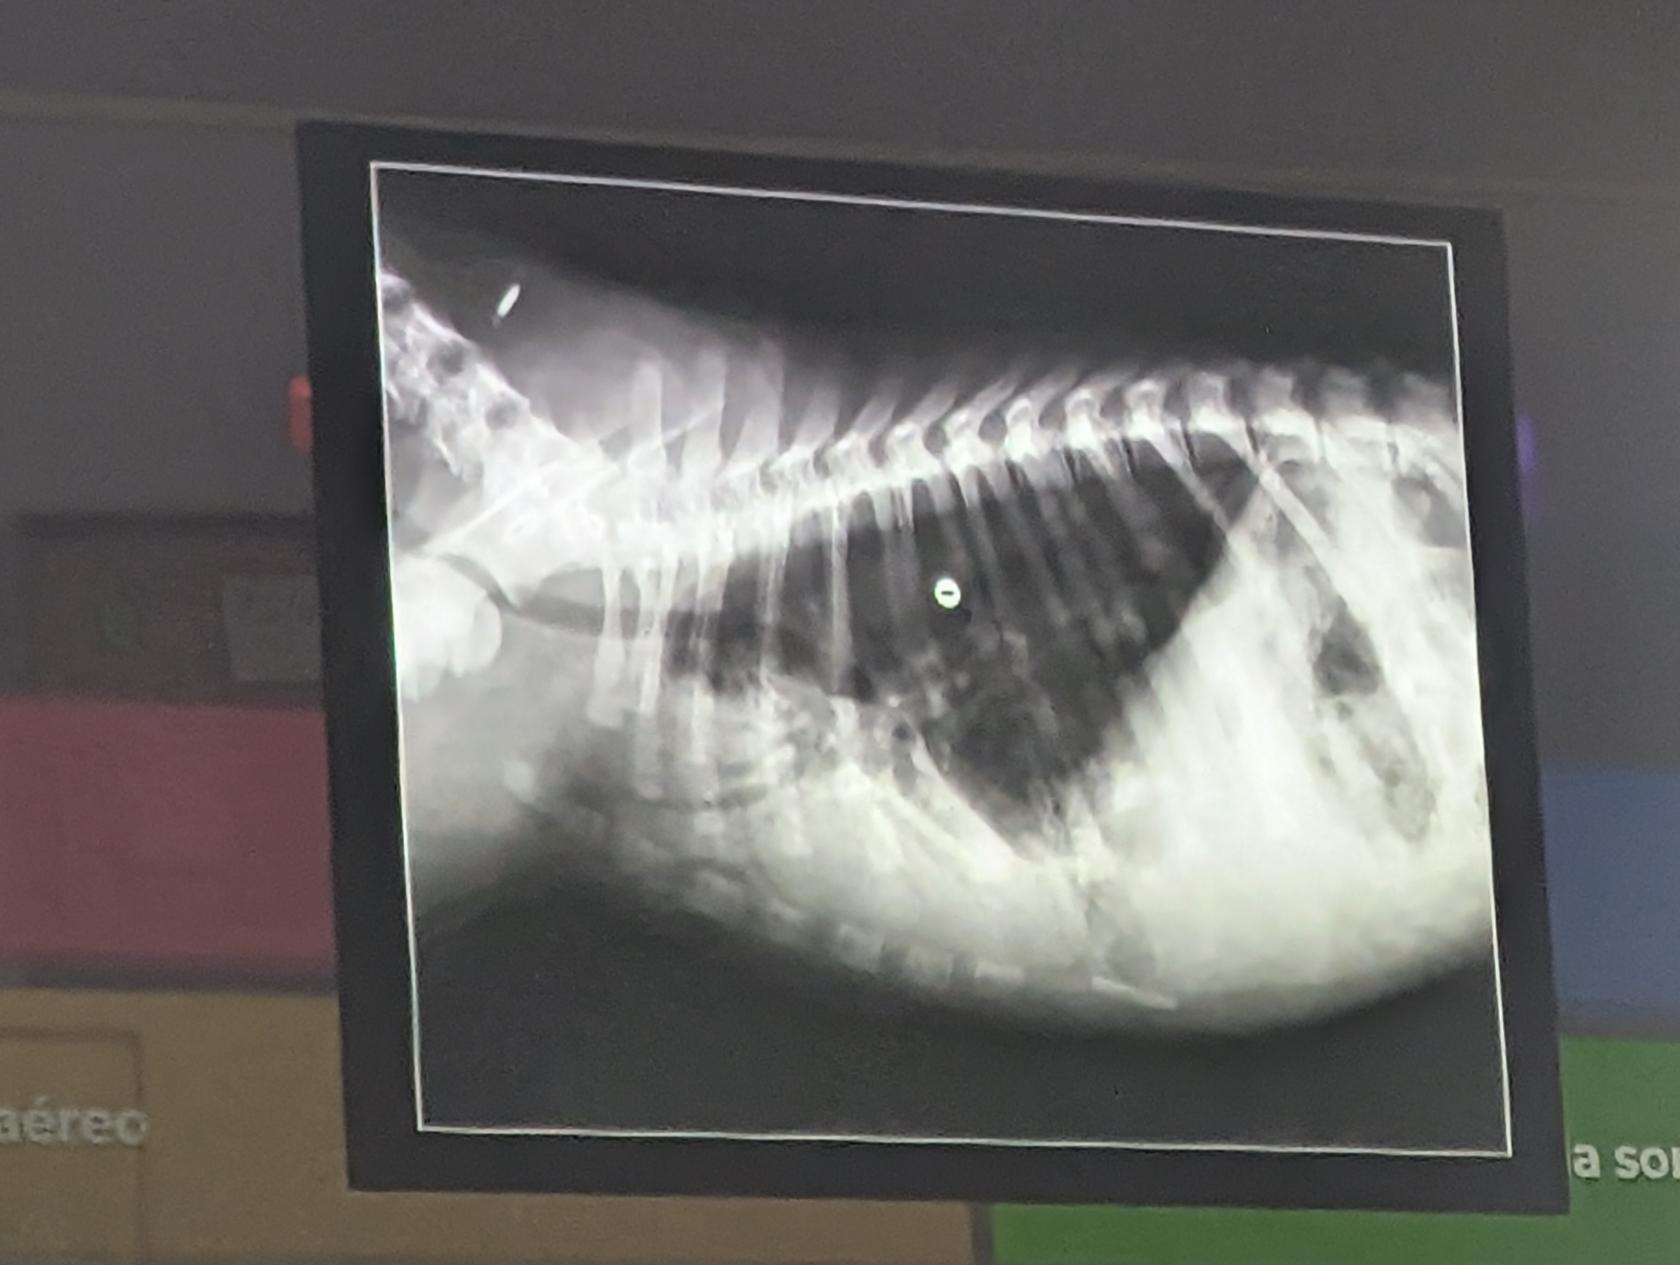

9) Una respuesta correcta

- Ninguna es correcta, es una radiorafia normal